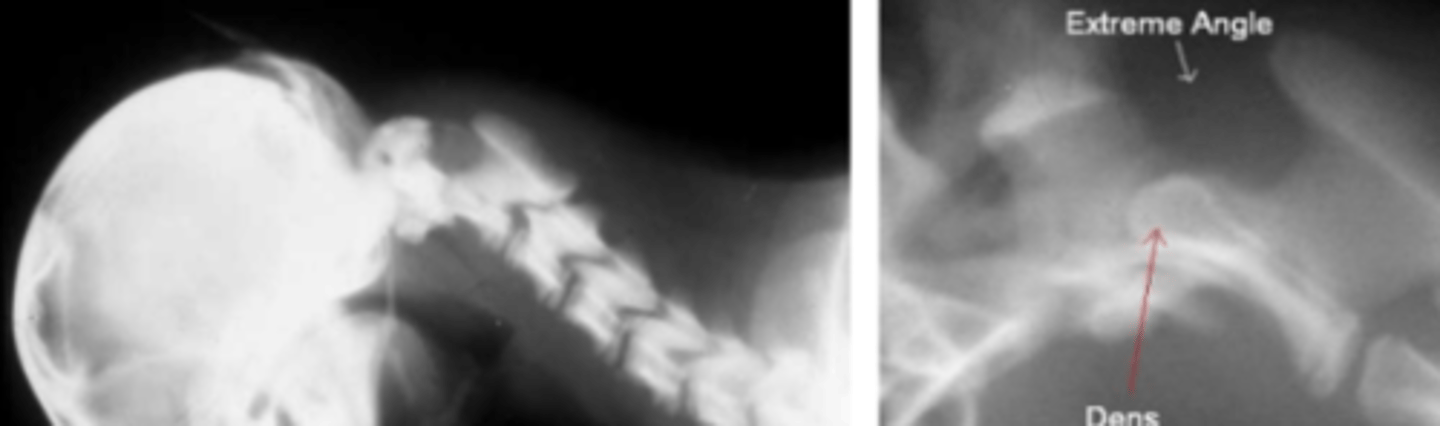

What is the pathogenesis of AA luxation?

- Hypoplastic dens/stabilizing ligaments of the atlantoaxial joint

What animals are commonly affected by AA luxation?

- Toy breed dogs

Describe the typical clinical presentation of AA luxation.

- Low head carriage

- Tetra paresis and tetra ataxia in all four legs

- Inability to stand or move the legs

- Difficulty breathing

What dogs with AA have a better prognosis?

- Dogs with shorter duration of signs

How is AA repaired?

- Screws and PMMA cement work best

What are some complications of AA repair?

- Breathing difficult

- Pneumonia

- Implant migration

- Collapsing trachea

- Hemorrhage (Blood vessels running through vertebrae)

Dogs with untreated AA die from...

- Can get kinking and edema of brain stem -> Death